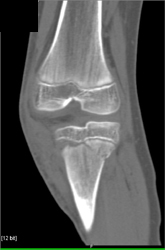

Diagnosis

Sacral and Acetabular Fractures